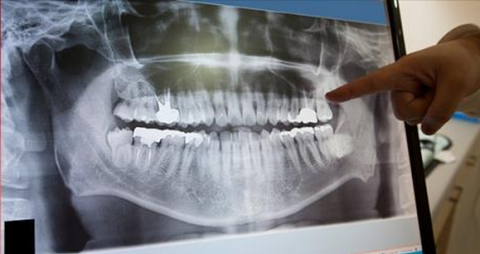

Dental X-Rays Are Safe

One of the most common things done at a routine dental visit is having x-rays. It’s those x-rays that allow the dentist to take a closer look at the overall health of your teeth to detect damage and disease affecting the roots and bones of your mouth, and to look for any possible cavities – things that aren’t visible during a routine visual exam. Sounds good, right? But then we cover you in a heavy vest and ask pregnant women to forgo x-rays which prompts lots of questions from our patients about dental x-ray safety. So, let’s talk about it!

The worrisome part about dental x-rays is the exposure to radiation. Radiation is a scary term, but the reality is that we are exposed to radiation in our everyday lives, not just during x-rays. Radiation is measured in units called rems. The doses in the medical world are so small, they are measured in millirems, or “mrem” which is just one thousandth of a rem. Below are some examples of amounts of radiation we’re exposed to in our everyday lives*: